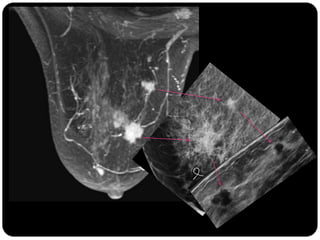

Paciente femenina de 66 años con historia clínica de 1er gesta antes de los 30 años y antecedentes de lactancia positiva, presenta una lesión palpable en la mama derecha. Los estudios radiológicos indican un diagnóstico de bi-rads 5, con biopsias revelando adenocarcinoma lobulillar infiltrante en la glándula mamaria derecha y adenocarcinoma ductal in situ en la izquierda. El caso fue evaluado por las doctoras Jacqueline Preciado Vargas y Beatriz E. González Ulloa.